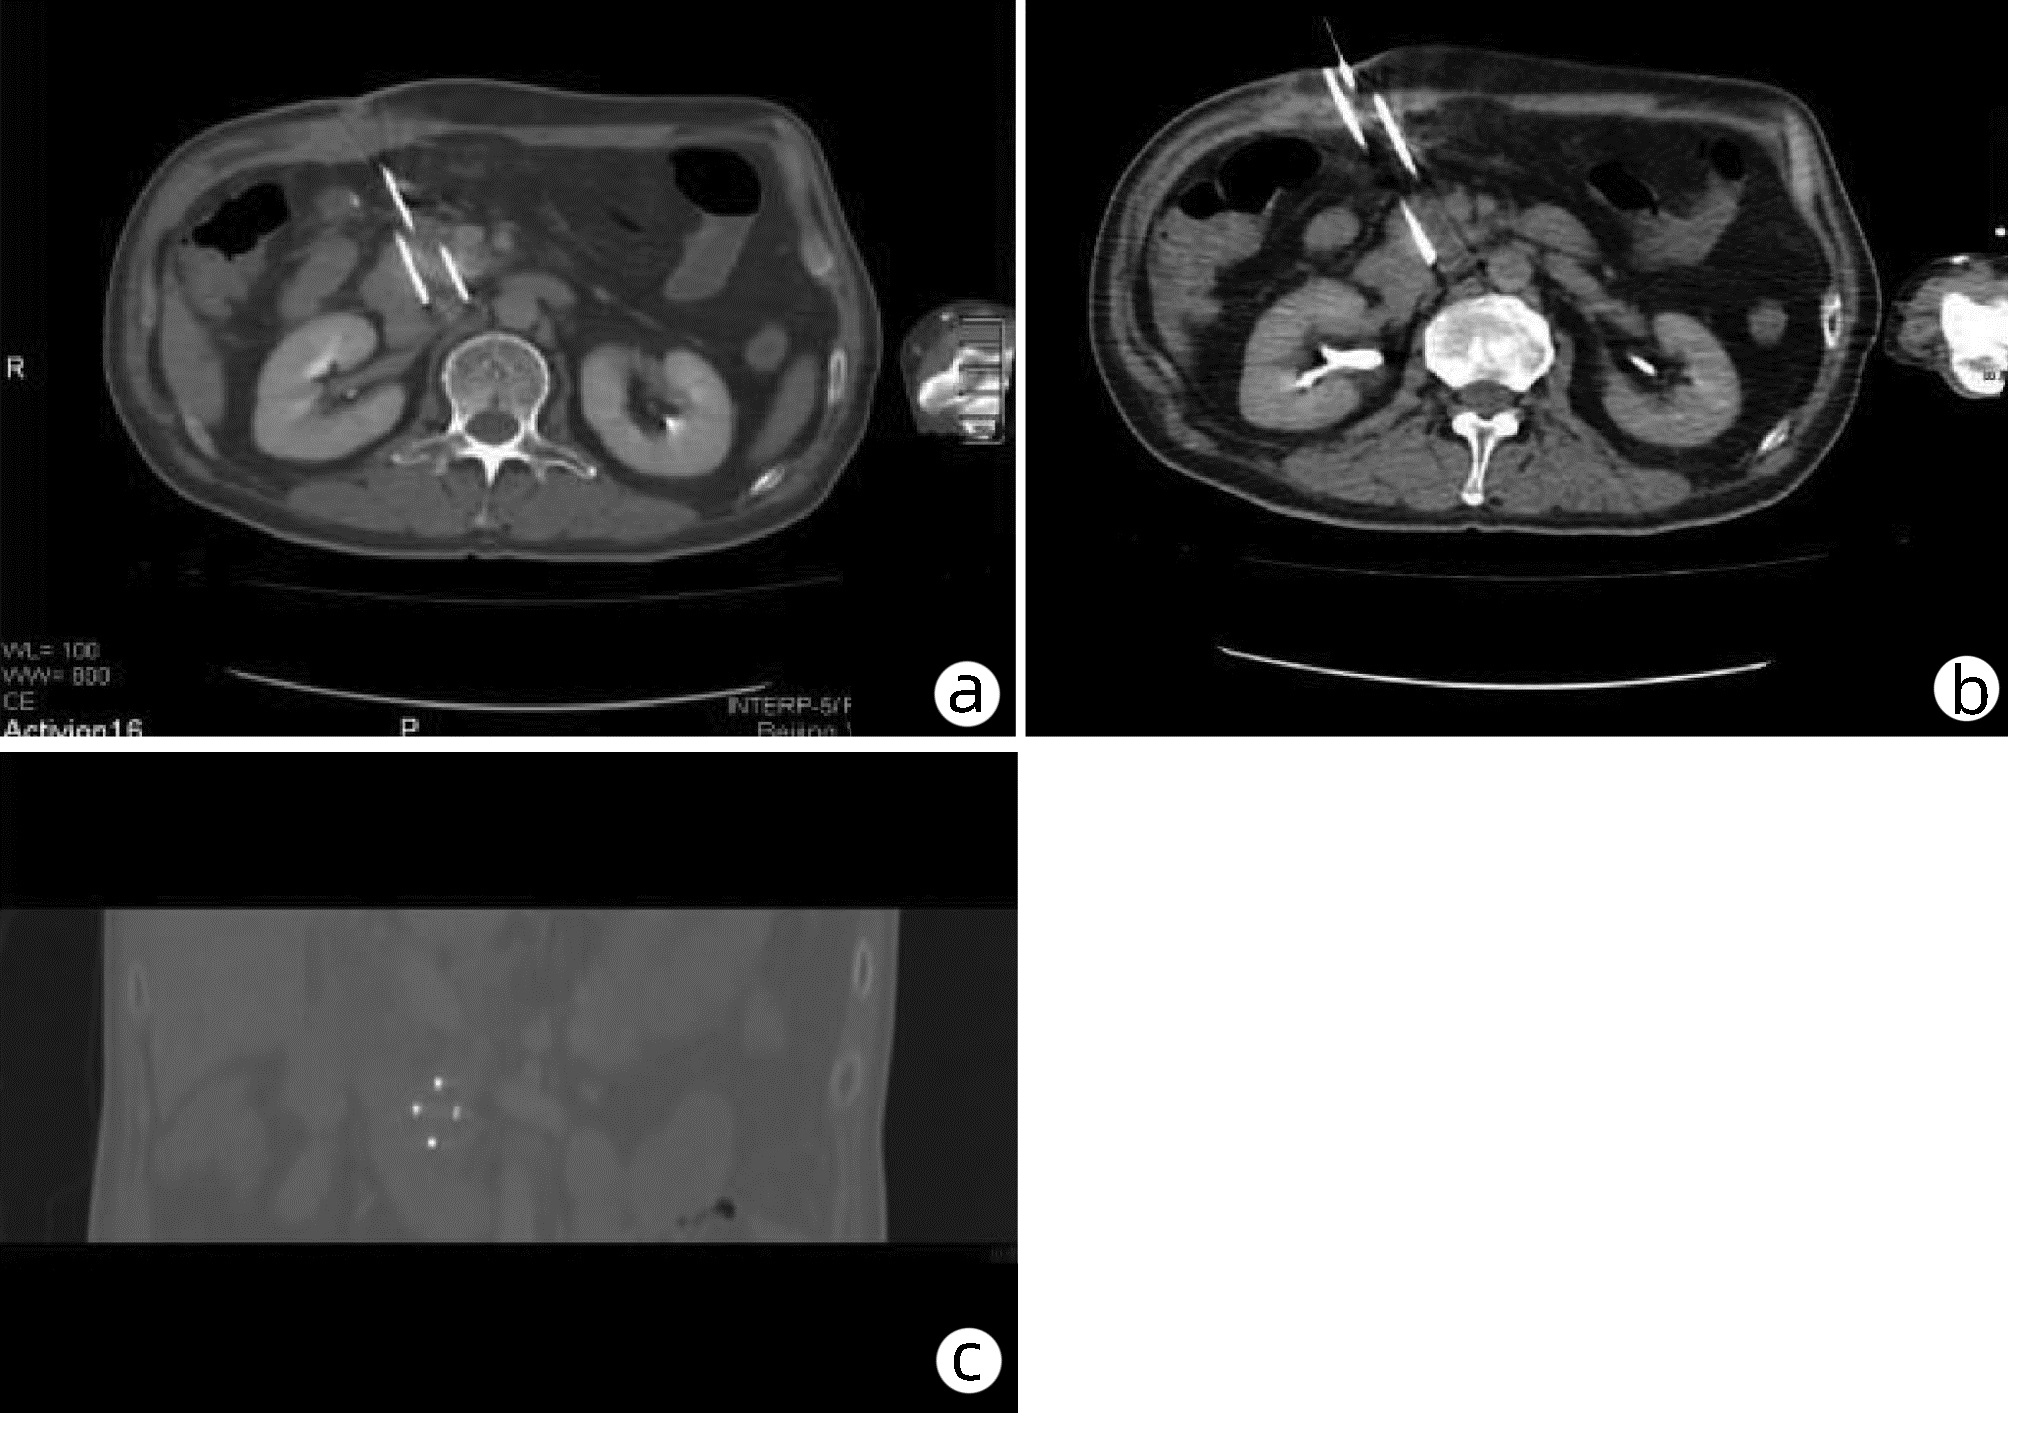

肝动脉栓塞联合射频消融间隔时间对小肝癌临床疗效的影响

孙玉, 张洪海, 龙江, 生守鹏, 郑加生, 张永宏

2022, 38(10): 2286-2289. DOI: 10.3969/j.issn.1001-5256.2022.10.016

摘要(1078) HTML (284) PDF (1758KB)(66)

摘要:

目的  研究肝动脉栓塞联合射频消融两种治疗时间间隔对小肝癌临床疗效的影响。  方法  选取2019年1月—2020年6月于首都医科大学附属北京佑安医院接受治疗的肝细胞癌患者70例。采用随机数字表法将患者分为观察组(肝动脉栓塞治疗当日或第2日序贯射频消融)和对照组(肝动脉栓塞治疗后1~2周序贯射频消融),每组各35例。计量资料两组间比较采用独立样本t检验,术前与术后观察指标比较采用配对t检验;计数资料两组间比较采用χ2检验。  结果  观察组住院时间短于对照组,差异有统计学意义[(7.80±2.76) d vs (14.31±2.19) d,t=-10.93,P<0.001}。观察组与对照组完全消融率(95.12% vs 95.00%,χ2 =0.001,P=0.980)、不良反应发生率(25.71% vs 20.00%,χ2 =0.324,P=0.569)及1年复发率(11.43% vs 14.29%,χ2 =0.128,P=0.721)比较,差异均无统计学意义。对照组术前术后实验室指标与观察组术前术后比较,差异均无统计学意义(P值均>0.05)。  结论  肝动脉栓塞短期序贯射频消融治疗小肝癌安全有效,可明显缩短患者住院时间,减少住院花费,值得临床推广。